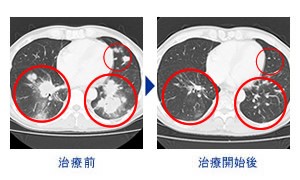

HANIL BIOTECH有限公司_治疗案例

肝内胆管癌症-照片

肝内胆管癌症

+肺转移(57岁男性)NK细胞5回注射

+PD-1免疫抗癌剂(抗PD-1抗癌剂)

+易普利姆玛(抗CTLA-4抗癌剂)5回注射

HANIL BIOTECH有限公司_治疗案例

肾盂癌(肾盂癌系发生在肾盂或肾盏上皮的 恶性肿瘤)案例 – 照片

肾盂癌右边支气管

纵隔淋巴结转移(65岁 男性)NK细胞2疗程10回注射

PD-1免疫抗癌剂(抗PD-1抗癌剂)2疗程10回注射

+ 易普利姆玛(抗CTLA-4抗癌剂)2回注射